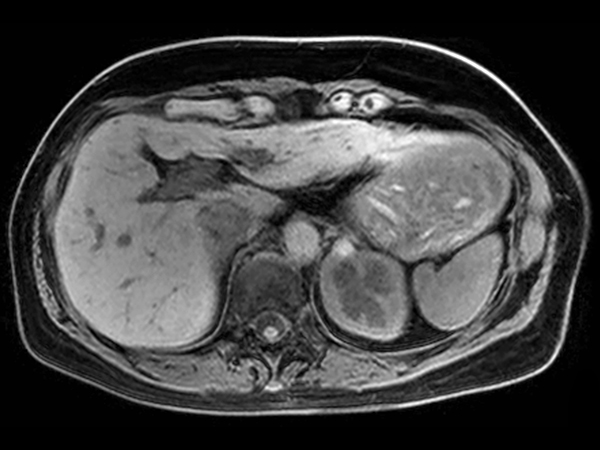

Axial T2w SPAIR dS SENSE = 4.5, MobiView